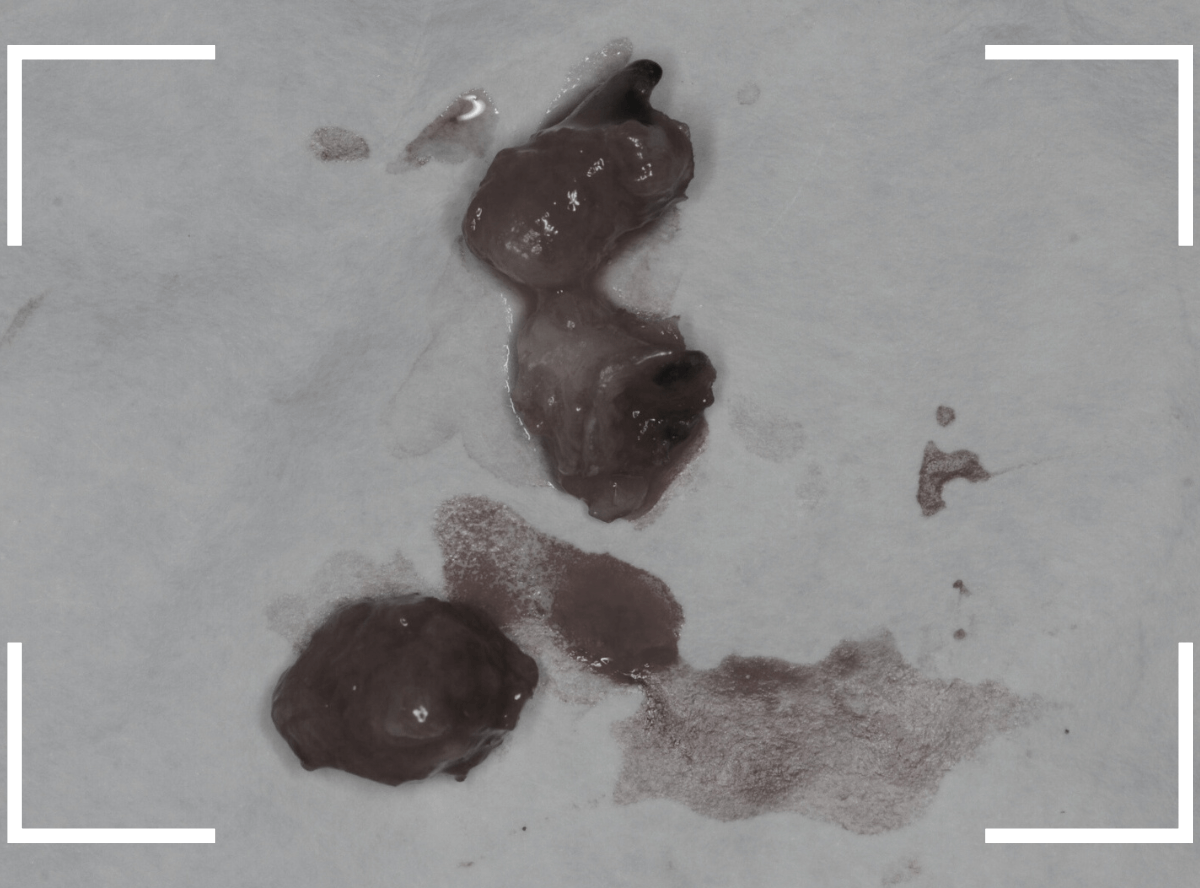

こちらが、抜歯後の写真です。

ここまで虫歯が進行していると、虫歯の治療をしても、ほとんど歯は残っていなかったでしょう。

歯の頭が無くなってしまうと、抜歯も困難にな行ってしまいます。

少しでも虫歯が進行しないうちに、と抜歯を行いましたが、やはりかなり手こずりました。

こちらが抜歯後のおやしらずの写真です。

根だけの状態になっていました(残根といいます)が、こちらは苦労なく抜歯できました。

抜歯した手前の歯をお見せして、

「半年くらい前に受診していたら、歯を残せたかもしれない」というお話をすると、残念がっていました。